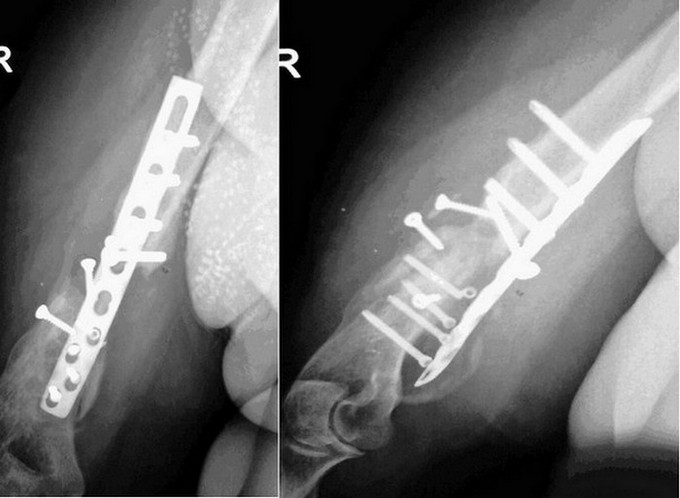

Пациентка 48 лет неоднократно оперирована по поводу перелома, а

впоследствии ложного

сустава плечевой кости.

Пациентка 48 лет, неоднократно оперирована по поводу перелома, а

сустава плечевой кости. Последний раз около года назад, резекция ложного

сустава с костной

пластикой из гребня подвздошной кости. Результат вы видите на снимках.

Из сопутствующей

патологии только ЭКО III ст. Поступила к нам в отделение для дальнейшего

лечения. По результатам анализов, и всех других обследований без

отклонений. Местно: как обычно патологическая подвижность, умеренная

болезненность, кожные покровы не изменены, не

считая розового рубца. Конечно же вопрос - что делать? Варианты: штифт?

Возможно... Костная пластика снова? Может АВФ с резекцией ложного

сустава? Но почему-то хотелось бы этого варианта избежать, женщина

все-таки. Кто-то из коллег предложил заполнить интрамедуллярный канал

цементом и вставить штифт - большие сомнения в успехе мероприятия.